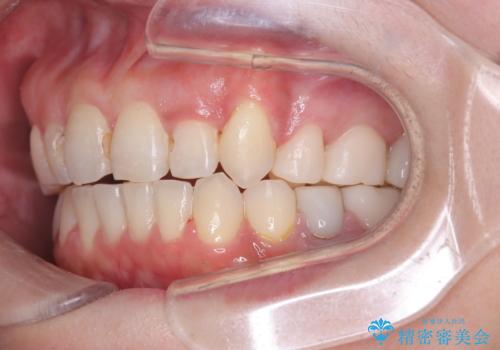

まず、計画通り左上4番を抜歯し、そのスペースを利用して八重歯を徐々に正しい位置へと移動させました。ワイヤー矯正特有の「歯を細かく、確実に動かす力」を最大限に活用し、歯根の向きまで丁寧に調整。

治療が進むにつれ、突出していた八重歯がスムーズに列に収まり、凹凸がなくなったことで、以前よりもブラッシングがしやすく清潔な口腔環境が整いました。治療完了後、長年のコンプレックスから解放された患者様の笑顔は非常に明るく、40代からでも遅くない「大人の矯正」の大きなメリットを実感していただける症例となりました。